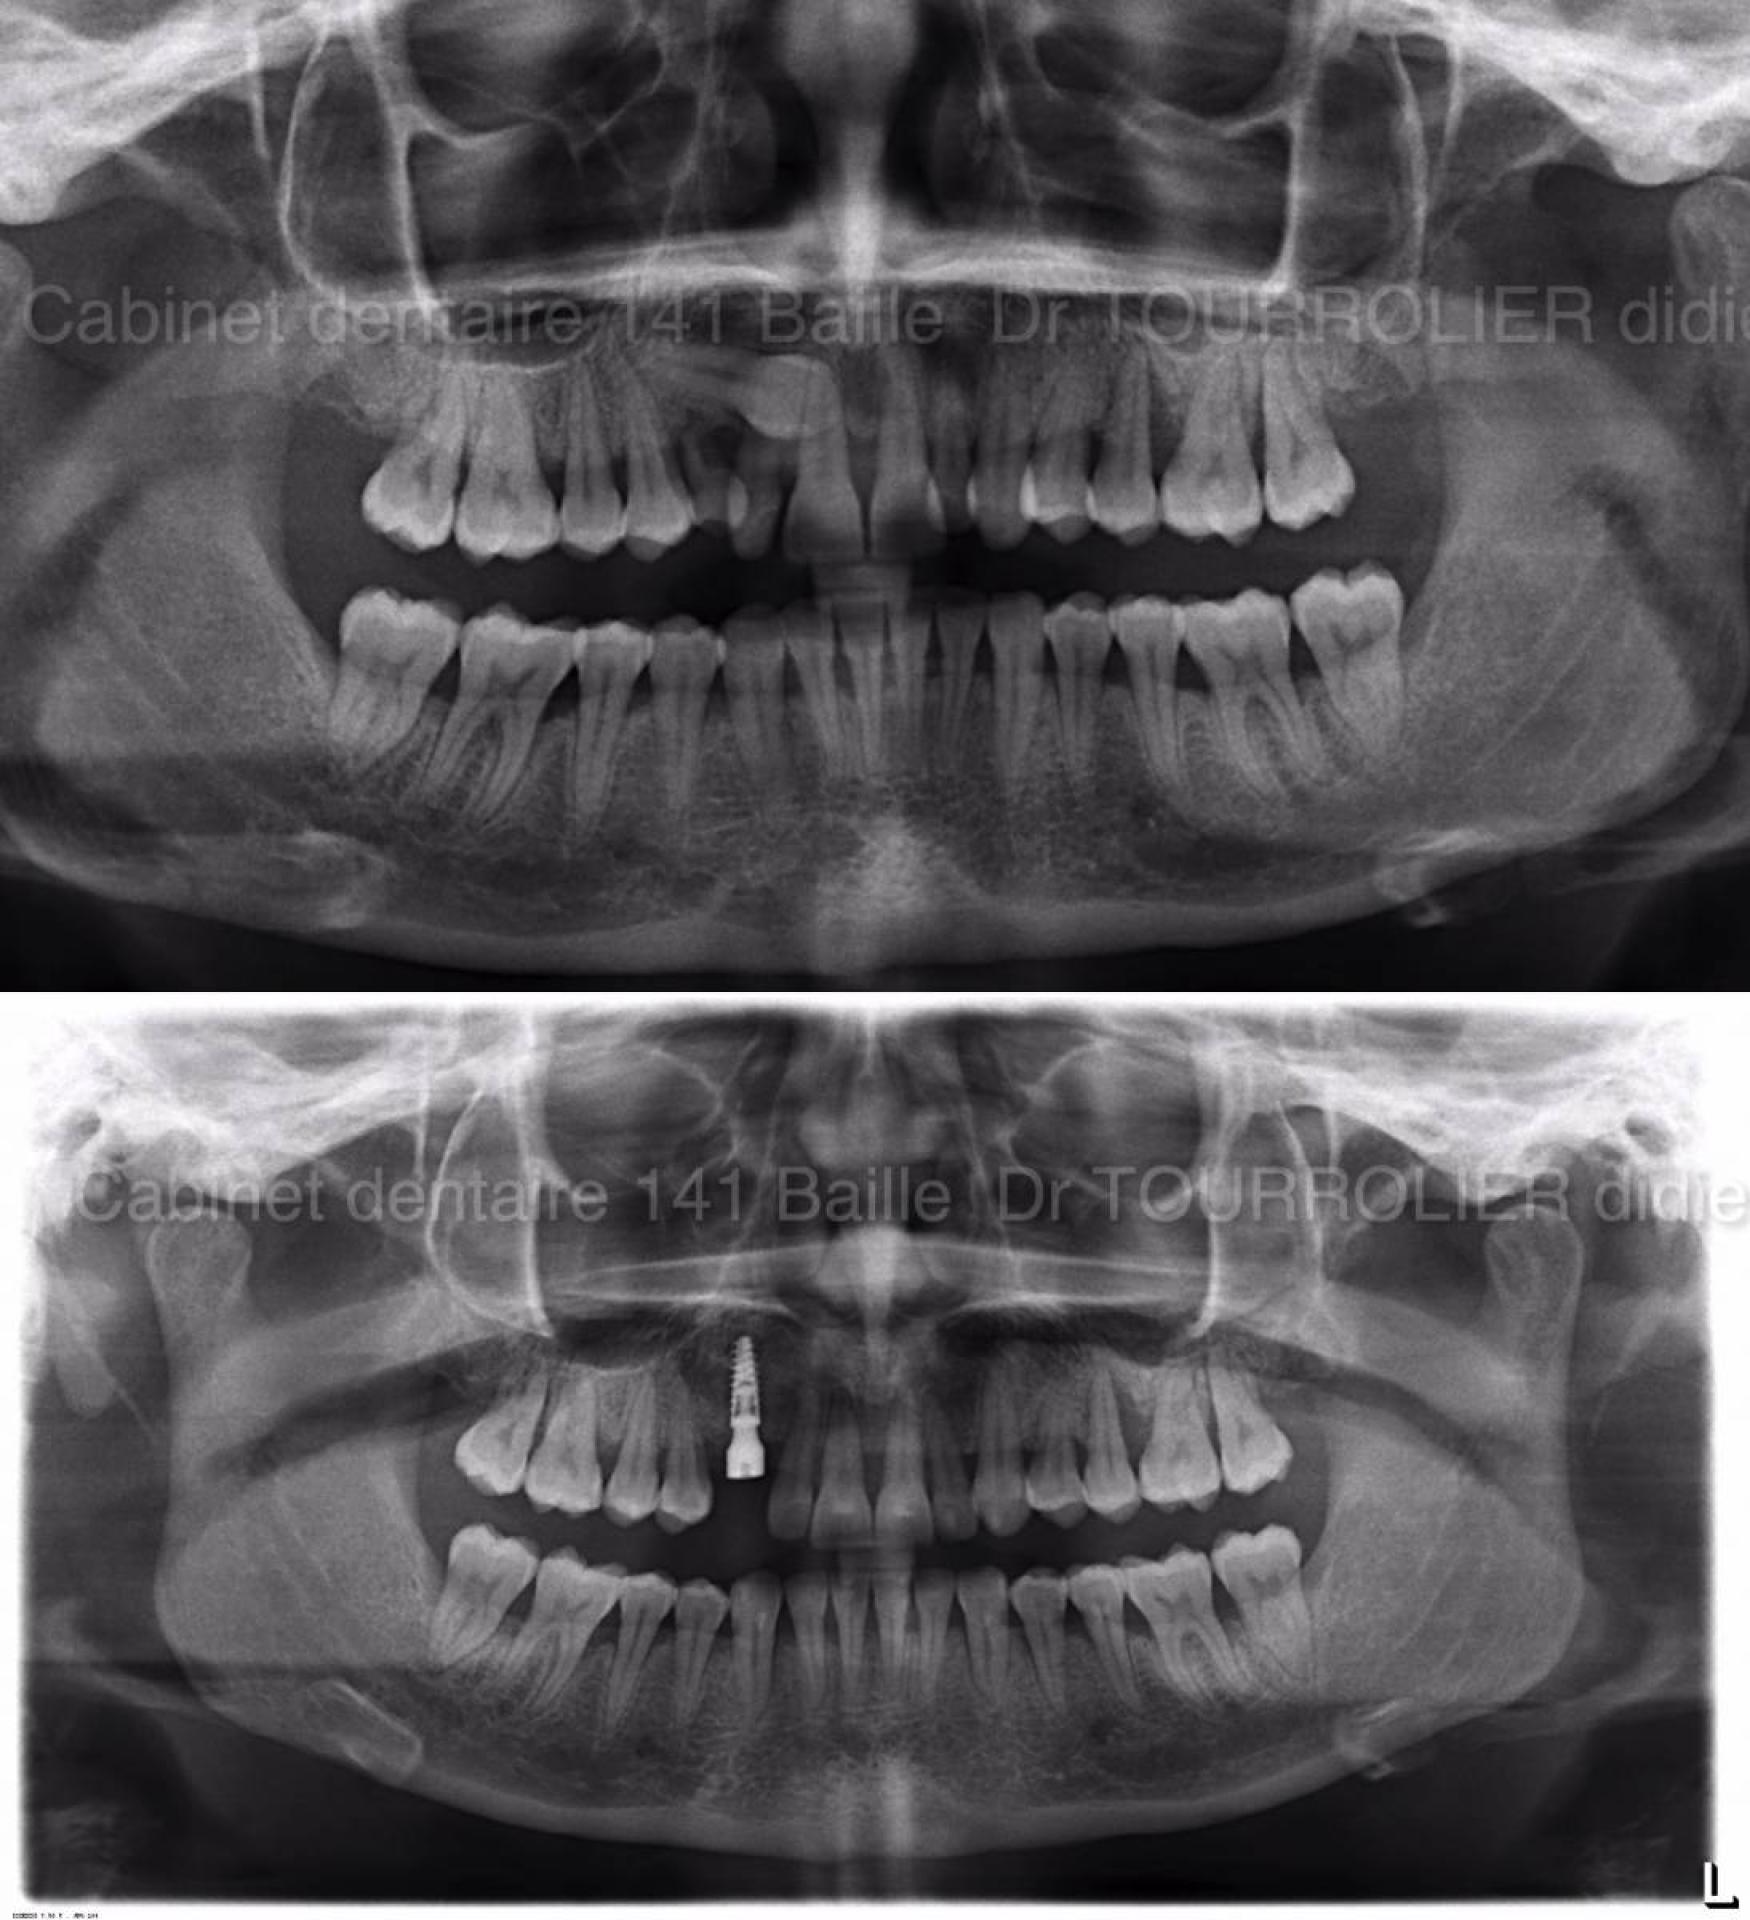

Dans le cas illustré la dent 13 est en situation palatine  en travers et fortement incluse .

Dans la même chirurgie ,il a été réalisé l'extraction par dégagement chirurgical de cette dent et la mise en place immédiate d'un implant combiné à une greffe osseuse dentaire de régénération.